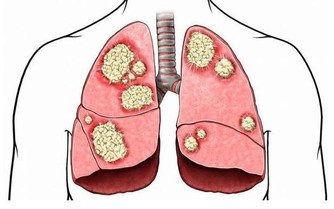

現在,肥胖的2型糖尿病人群是越來越多相關的數據表明,出現肥胖和超重T2DM的發生起著很大的影響作用。因為體重的或腰圍增加都會加重胰島素抵抗,增加T2DM的發生風險以及血糖控制的難度。對於一些降醣類型的藥物選不好的情況下,那就會大大增加出現體重增加的情況。

【降糖的時候還會出現體重增加的藥物】

1、胰島素。這作為一種很強並且有效的降糖藥物,因為胰島素出現增重的情況,是有著一定的劑量依賴性和個體差異性,同時在增重的方面也是有著很大的差異性。

2、噻唑烷二酮類的藥物。這種藥物主要是通過增加靶細胞對胰島素作用的敏感性作用,從而來幫助達到降低血糖的作用,經過了相關的研究數據表明,主要是能夠使糖化血紅蛋白下降到1.0%~1.5%,從而就引起體重得增加。

3、磺脲類的藥物。主要是通過刺激胰島β細胞分泌胰島素,增加體內胰島素水平來發揮降糖作用,但是可使糖化血紅蛋白降低1.0%~1.5%,從而就會引起體重增加的症狀。